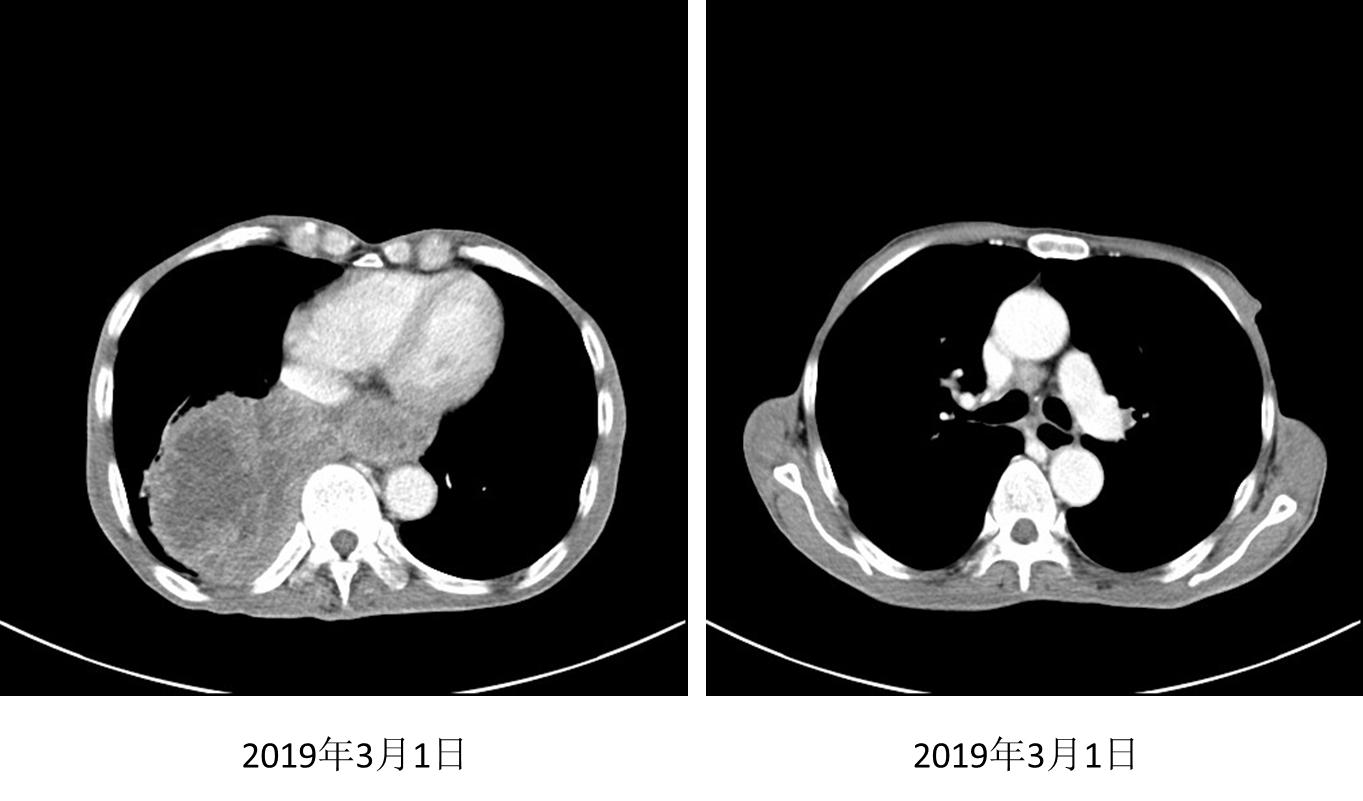

二线治疗

2018年12月至2月接受安罗替尼12mg/d治疗3个月;2019年3月1日复查,胸部肿块较前增大,且胸闷闭气症状加重,评价为疾病进展(PD)。

图3. 2019年3月1日胸部CT